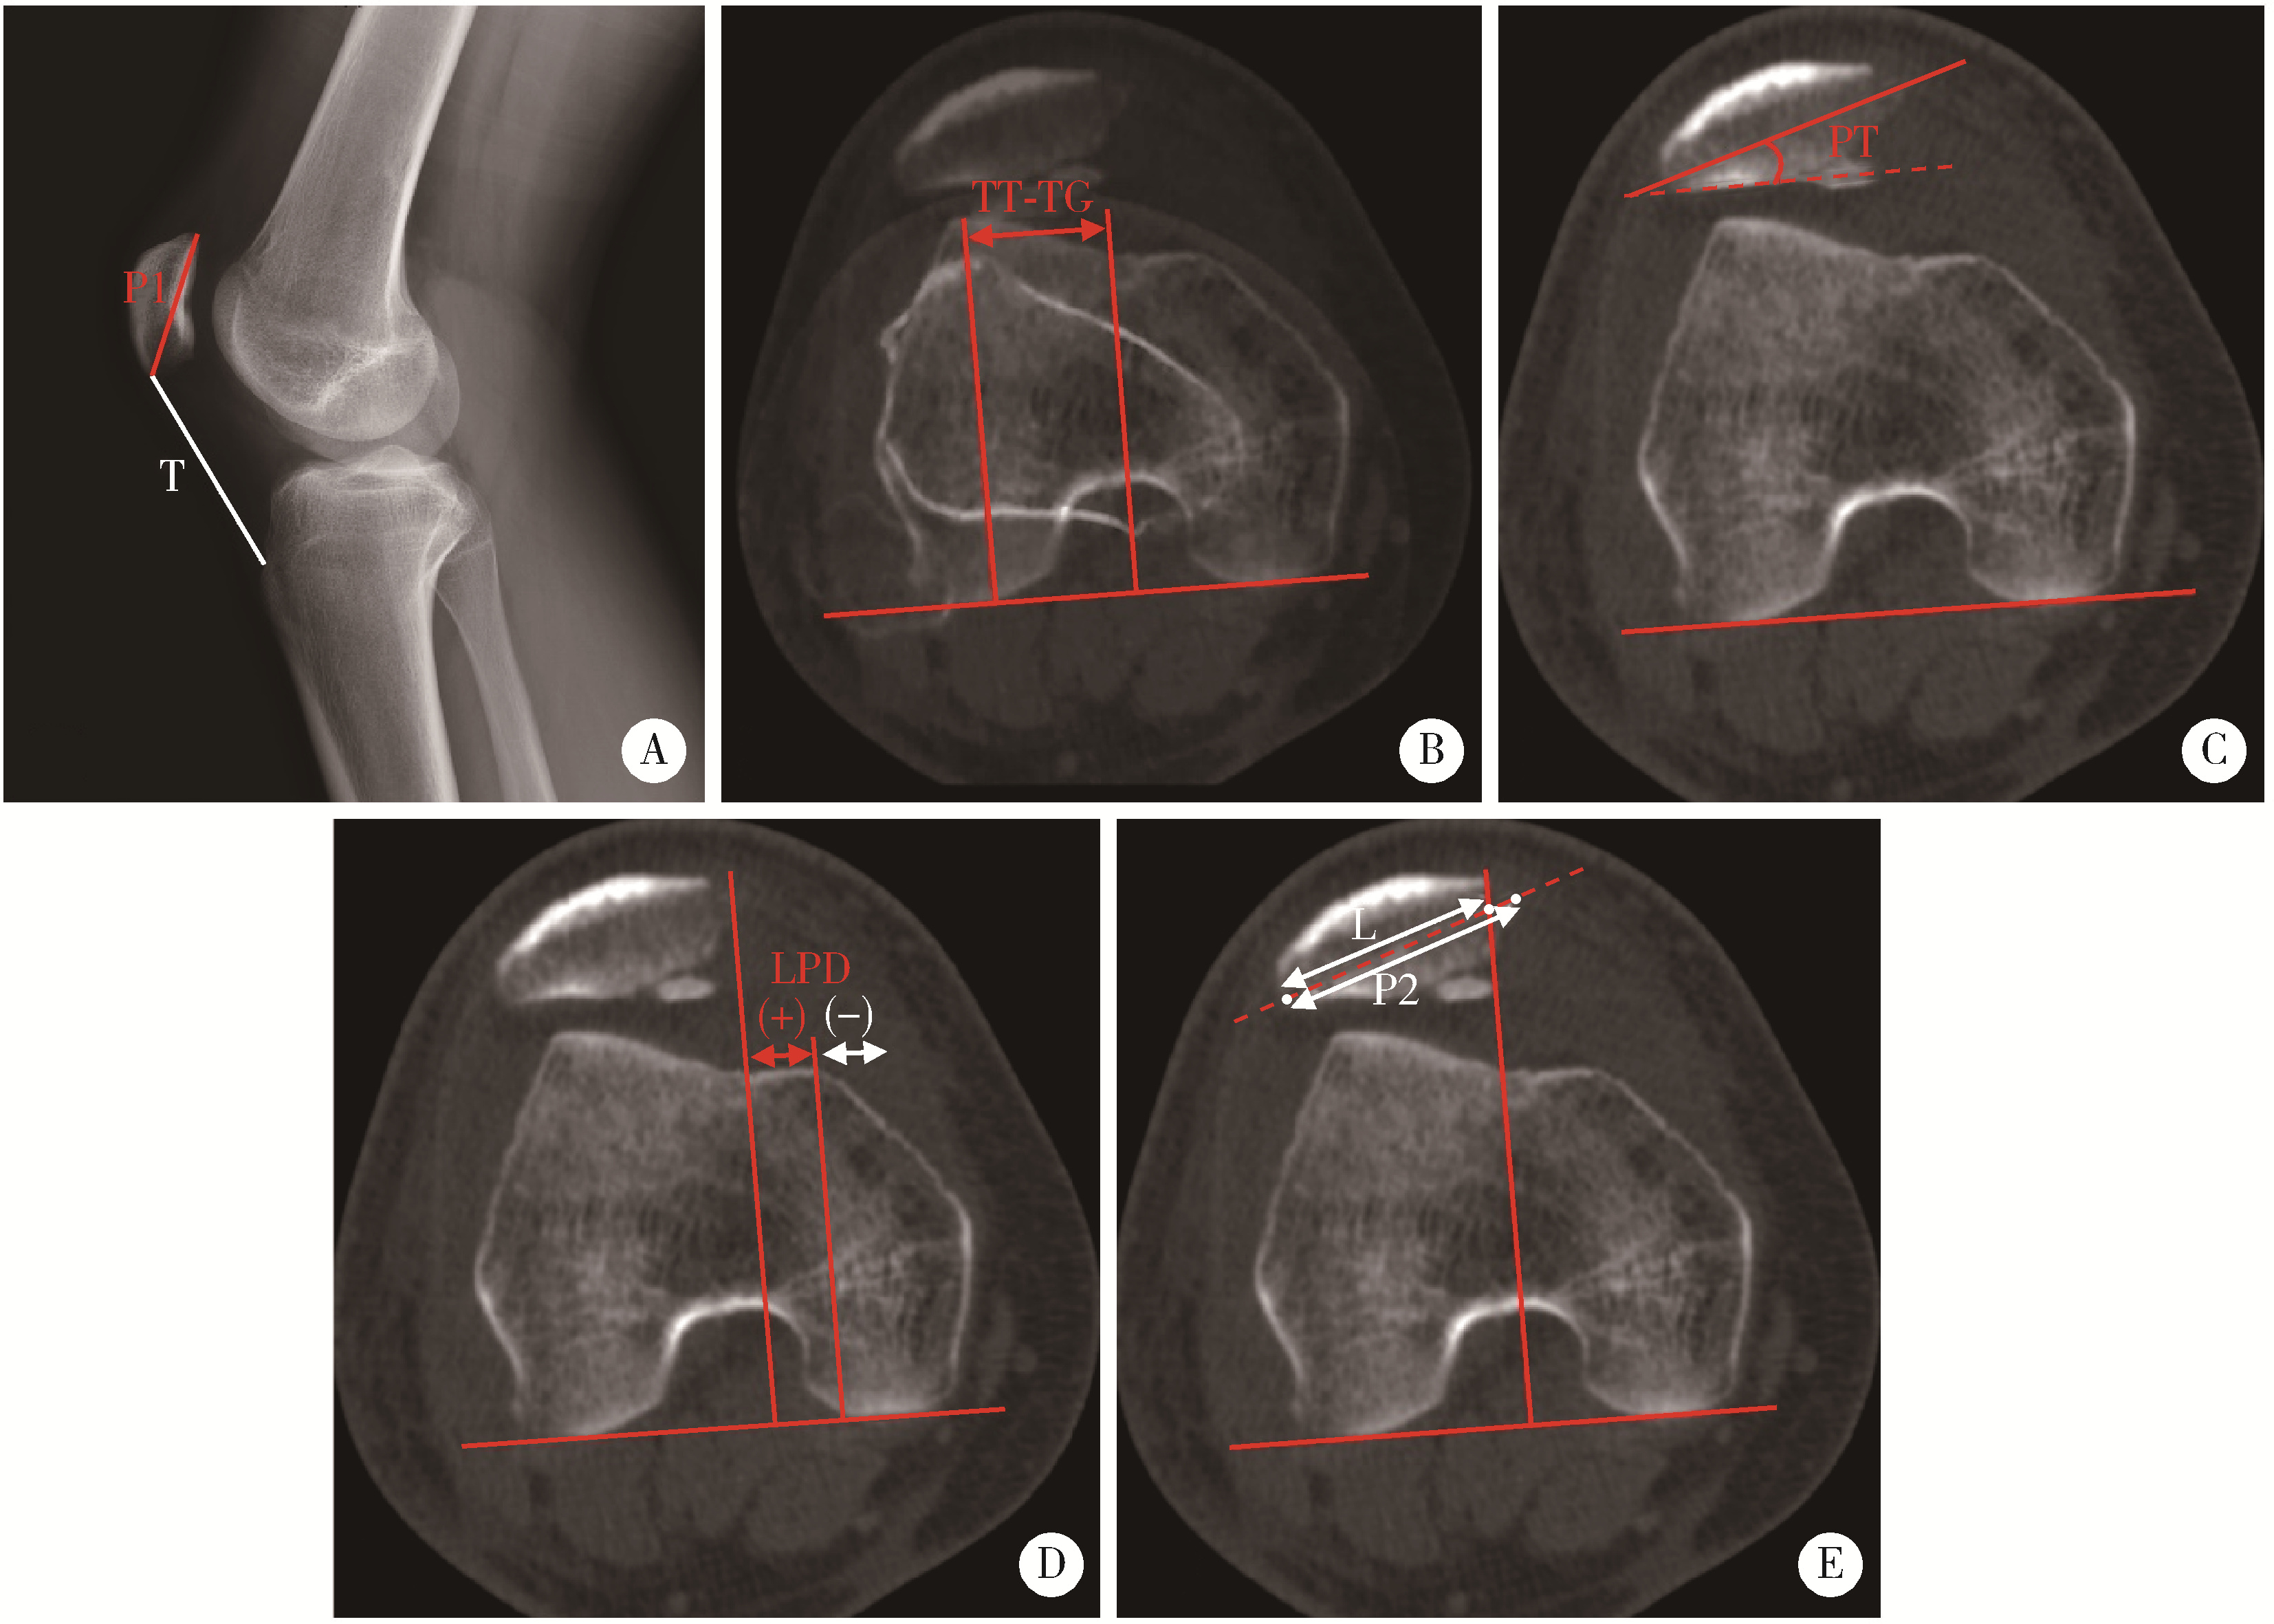

Figure 4

Comparison of axial CT scans of the patellofemoral joint before and after MPFC reconstruction Patient 1 was a 17-year-old male diagnosed with recurrent patellar dislocation of the right knee. Preoperative CT scan showed significant patellar tilt and lateral displacement, which were both corrected on postoperative scan. Patient 2 was a 16-year-old male diagnosed with recurrent patellar dislocation of the right knee. Preoperative CT scan demonstrated a dislocated patella with remarkable tilt and lateral translation, while the patellofemoral congruence was restored on postoperative scan. CT, computed tomography; MPFC, medial patellofemoral complex reconstruction."